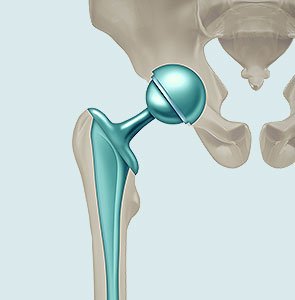

Przygotowanie do planowanej operacji ortopedycznej, takiej jak endoprotezoplastyka stawu biodrowego lub kolanowego, jest kluczowe dla bezpieczeństwa pacjenta i skuteczności leczenia. Odpowiednie przygotowanie obejmuje wykonanie niezbędnych badań, konsultacje specjalistyczne oraz dostosowanie stylu życia przed zabiegiem.

Specjalizuje się w całkowitej endoprotezoplastyce stawu biodrowego i kolanowego z wykorzystaniem nowoczesnych małoinwazyjnych technik operacyjnych , operacje stawu biodrowego z dostępu MIS DAA, zabiegi endoprotezoplastyki częściowej (jednoprzedziałowej) stawu kolanowego, zabiegi rewizyjne po endoprotezoplastyce stawów biodrowych i kolanowych , leczenie operacyjnie i nieoperacyjne złamań, artroskopia stawów, leczenie stawów z wykorzystaniem terapii komórkami macierzystymi, czynnikami wzrostu, wiskosuplementacją.